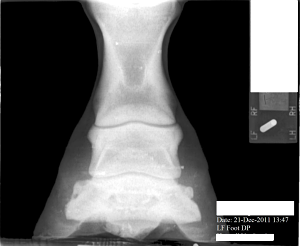

Posted on Friday, Jan 27, 2012 - 2:44 pm: The pastern joint doesn't appear to match the angle of the coffin joint or the fetlock joint...does it?What does this suggest? What else in these X-Rays would suggest 'trouble'? Mare is three and now in corrective shoes. Medial and Lateral balance was terrible. She is in a show barn and not worked a great deal and has little turn out. Thank you everyone.

Posted on Sunday, Jan 29, 2012 - 7:53 pm: Thanks Cheryl. It was late Friday when I posted, and I figured everyone would be off having a week end. Anyway, for what it's worth, I see the beginning possibly of side bone on the lateral side. I see the pastern joint angle does not match the angles of the fetlock and coffin joint. I cannot tell where the coffin joint is in relation to the coronary band. She has long under run heels and long toes. I don't know if the depth/shape of the collateral grooves tells me anything. The ski tip on the front of the coffin bone bothers me especially on a horse only 3. And is there a small bit or rotation down as well? I don't understand in the X-Ray why her sole appears to be bearing the weight and the hoof walls are off the ground. Is this really how she was prior to 'corrective' shoeing or is this X-Ray poorly taken or am I just poor at interpreting it. Or has her hoof mechanism sunk into the hoof capsule some? I do not have vet remarks for these X-Rays. |

Posted on Sunday, Jan 29, 2012 - 8:16 pm: left front The first X-Ray cut off the fetlock joint. This was not an editing error.The coffin joint looks uneven to me. Bigger space on the medial side. What does that mean? Nothing or something. I can't tell if this mare is built like a stack of playing cards or not(remember stacking cards like the wobbly Leaning tower of Pisa?). And how come the left lateral view the hoof wall is on the block but the right lateral view the hoof wall is off the block...is this an operator error or wonky foot? |

Posted on Tuesday, Jan 31, 2012 - 8:12 am: Hello Vicki,In general I avoid interpreting radiographs on the internet as the quality of the images here are not high enough to do a good job and the amount of time required to look at all aspects of the radiograph. I do invite members to put up radiographs and I will comment on any diagnosis made by the veterinarian who took the radiographs. That said I do think the RF foot in the front appears to have an overly long toe and corresponding toe flare and underrun heel. I don't see these issues in the L fore. The problem with assessing the conformational issues your bring forth is that technique and how the radiographs are taken can greatly effect the relationship between the bones and create false impressions. For instance all a horse has to do is stand a little forward over the foot and the normal pastern will not be aligned. The conformation issues you raise are best assessed looking that the horse while standing square and moving in a straight line than by a static set of radiographs. DrO |